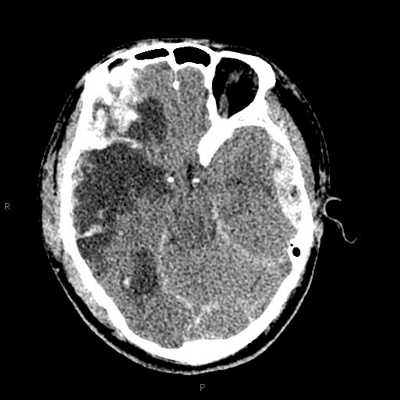

頭部CT圖,顯示顱內出血,但外表無流血。 |

2)當鈍性損傷發生在頭部、頸部、胸、腹部等軀幹部位時,需要高度重視,因為這些部位深,在損傷時,由體表很難發現具體症狀。因此建議立即就診,並由專業的醫護人員進行詳細體格檢查,甚至進行一些必要的影像學檢查。